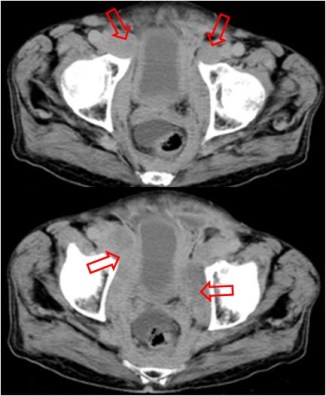

Signo visible en la urografía intravenosa o la cistografía de una mujer, correspondiente a una impresión en el suelo vesical similar a la impronta prostática del varón. Puede ser producida por lesiones neoplásicas o inflamatorias de la zona.

La imagen de TC corresponde a la misma paciente de la urografía, que presenta un tumor de cuello uterino -flechas negras- que infiltra la vejiga. Se trataba de un adenocarcinoma mucosecretor. La imagen recuerda a la impronta prostática en el TC.

Otro ejemplo de este signo en una paciente con hipertrofia del músculo elevador del ano.